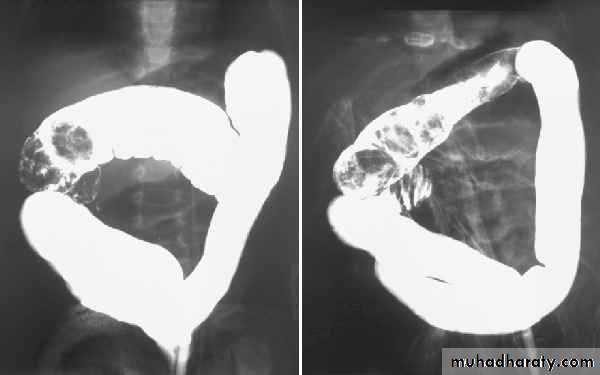

A barium enema shows annular carcinomas as an irregular stricture with shouldered edges (apple-core appearance), usually < 6 cm in length. The polypoid or fungating carcinoma causes an irregular filling defect projecting into the lumen of the bowel.